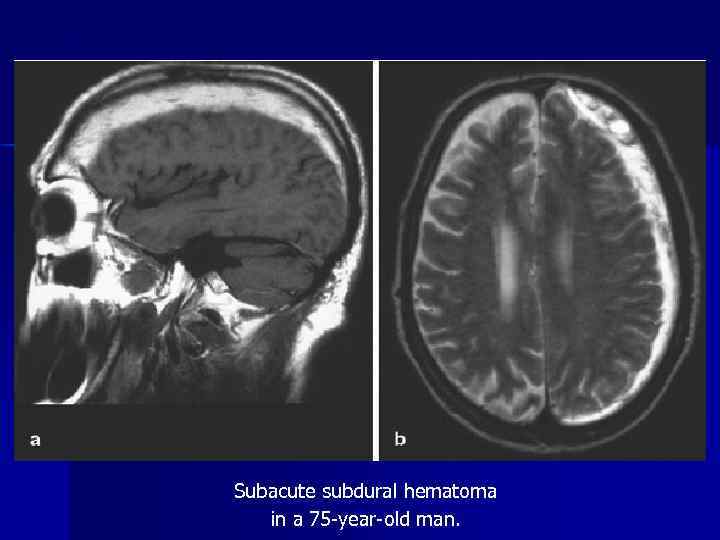

Subacute subdural hematoma in a 75 -year-old man.